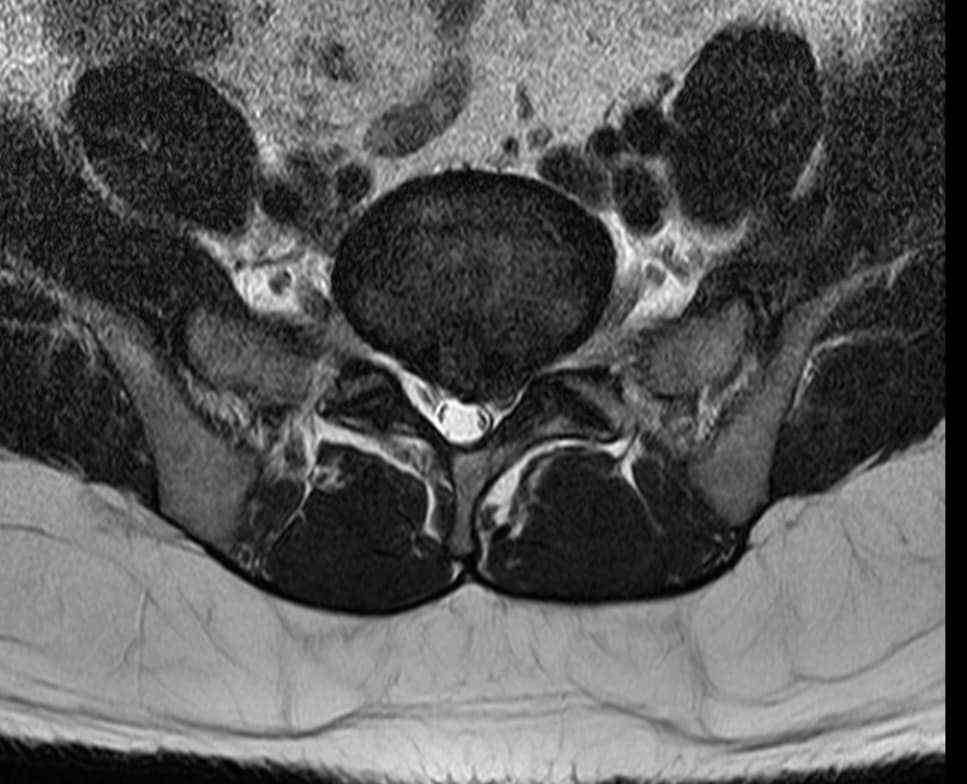

아래 첨부한 사진이 제 MRI 사진인데 집에서 요가매트로 간단하게 할만한 스트레칭 자세 추천해주실수있을까요?